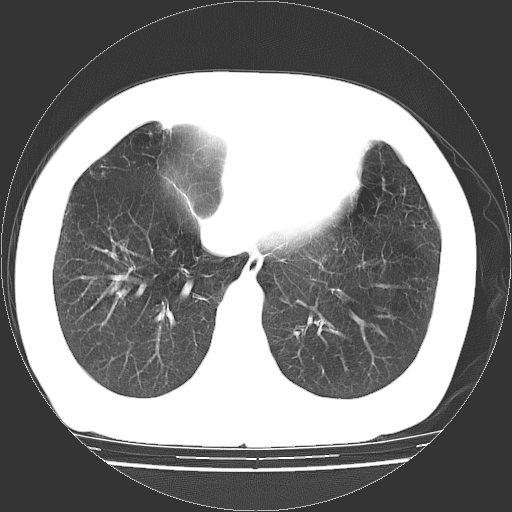

标题: CT13141:女,70岁,咳嗽、胸闷半个月。 [打印本页]

标题: CT13141:女,70岁,咳嗽、胸闷半个月。

女,70岁,咳嗽、胸闷半个月。纵隔窗未见异常,未上传。

小叶中心型肺气肿并多个肺大泡形成。

小叶中心性肺气肿及间隔旁肺气肿.(多与吸烟有关)

慢性支气管炎合并小叶中心性肺气肿及间隔旁肺气肿.(多与吸烟有关)。